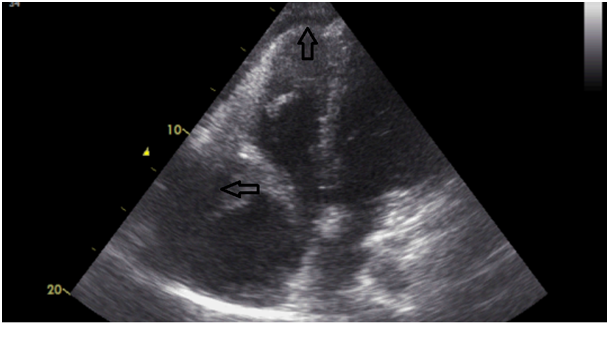

27years old male patient admitted to our outpatient clinic with progressive, pleuritic chestpain unrelated to exertion for a month with no significant medical history. The patient was diagnosed with acute pericarditis at an center and receiving ibuprofen and colchium treatment for three weeks. There was no pathological finding on cardiacaus cultation, blood pressure was 110/80mmHg, heart rate was 110bpm. Electrocardiography showed sinustachicardia and minimal ST segment elevation in all leads. There was a slight cardiomegaly in chest X-ray (Figure 1). Cardiac markers and inflammatory marker were elevated; troponin-I 1112ng/L (0-100), CK748 U/L (0-190), CK-MB 95 U/L(3-25), ESR 65, CRP 75 was detected. Transthorasic echocardiography revealed a 45x60 mm of cavitary mass compressing the right atrial free wall along with pericardial effusion (Figure 2); which was the only location of pericardial effusion in his previous examination a month ago. The patient was admitted to CCU. An aneursym 100x70x60mm in diameter, originating from right coronary artery extending to right atriallateral wall border and compressing externally, which contains thrombus material in its cavity was detected in cardiac computed tomography (CT) (Figure 3). Coronary angiography revealed a giant aneurysm communicated with RCA (Figure 4) without any abnormalty on left coronary arteries. The patient was given to emergency surgery because of the risk of pericardial tamponade. Aneurysmectomy was done and the remained cavity was closed primarily. Pathological examination was reported as polymorpho nuclear leukocyte and mononuclear inflammatory cell infiltration without elastic fibers and a pseudoaneursym of the coronary artery. The patient was discharged without any complication.

Figure 2 The cavitary mass compressing right atrium and the pericardial effusion.